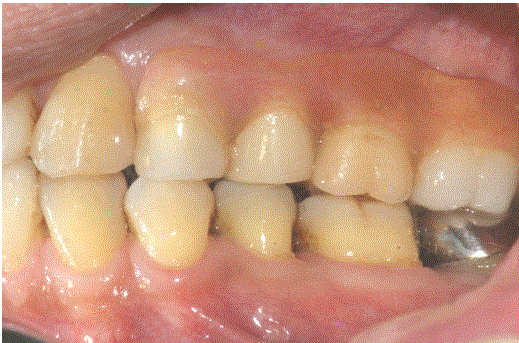

在根分离(#17)后(#17)构建左侧上颌部分CSC-套筒义齿单元(# 14 - #17)的磁性附着内冠(#15)(图1)。图2为部分CSCTD的横视图。带磁性附着体的CSCTD的颊侧和腭侧切面见图3和图4。图4为内冠(#14、#15、#17)的面部视图(图5)、右后视图(图6)和后颊面csc -望远外冠的外观(图7)。

图7:13年后(2019年),后颊面出现#14、#15和#17的外套筒冠。